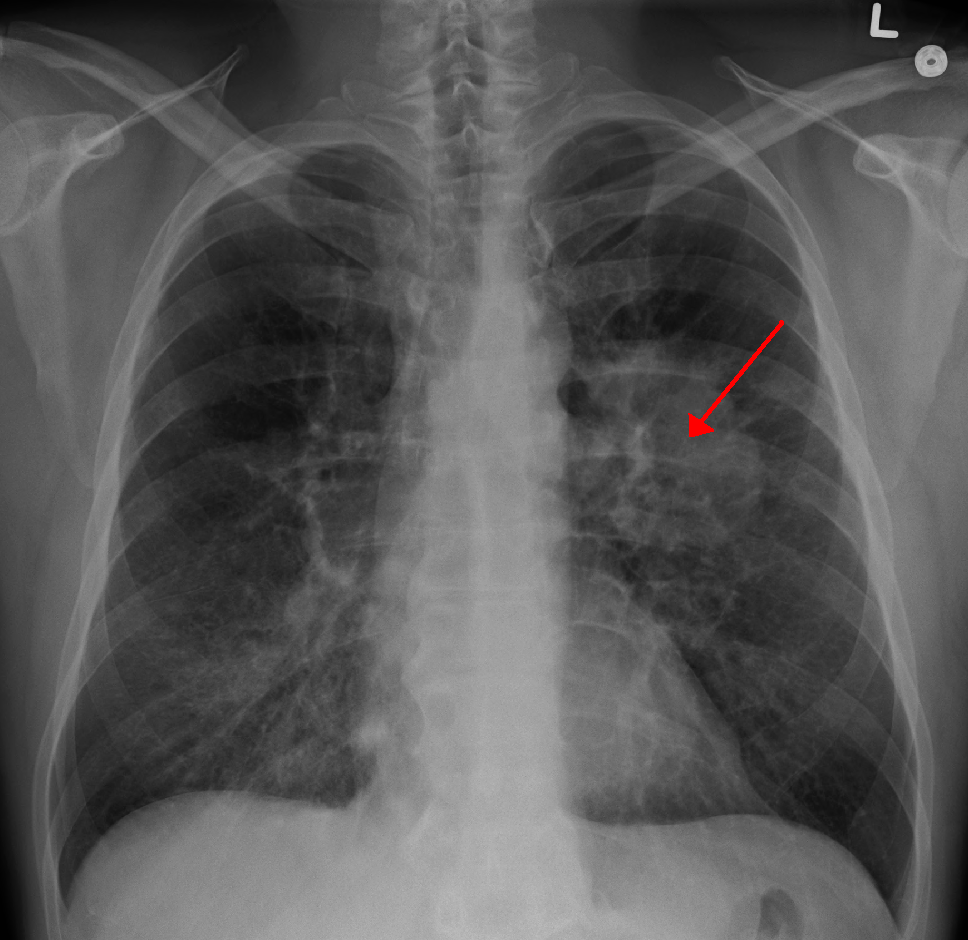

미세먼지는 폐로 들어가 염증 반응을 유발하고, 이로 인해 폐암을 유발하는 유전자의 돌연변이를 촉진합니다. 특히, 상피세포성장인자 수용체(EGFR) 유전자 돌연변이에 의한 폐암 발생률이 높아지는 것으로 확인되었습니다. 이는 비소세포성 폐암 환자의 약 50%에서 EGFR 변이가 발견되는 아시아 지역에서 특히 주목할 만한 결과입니다.